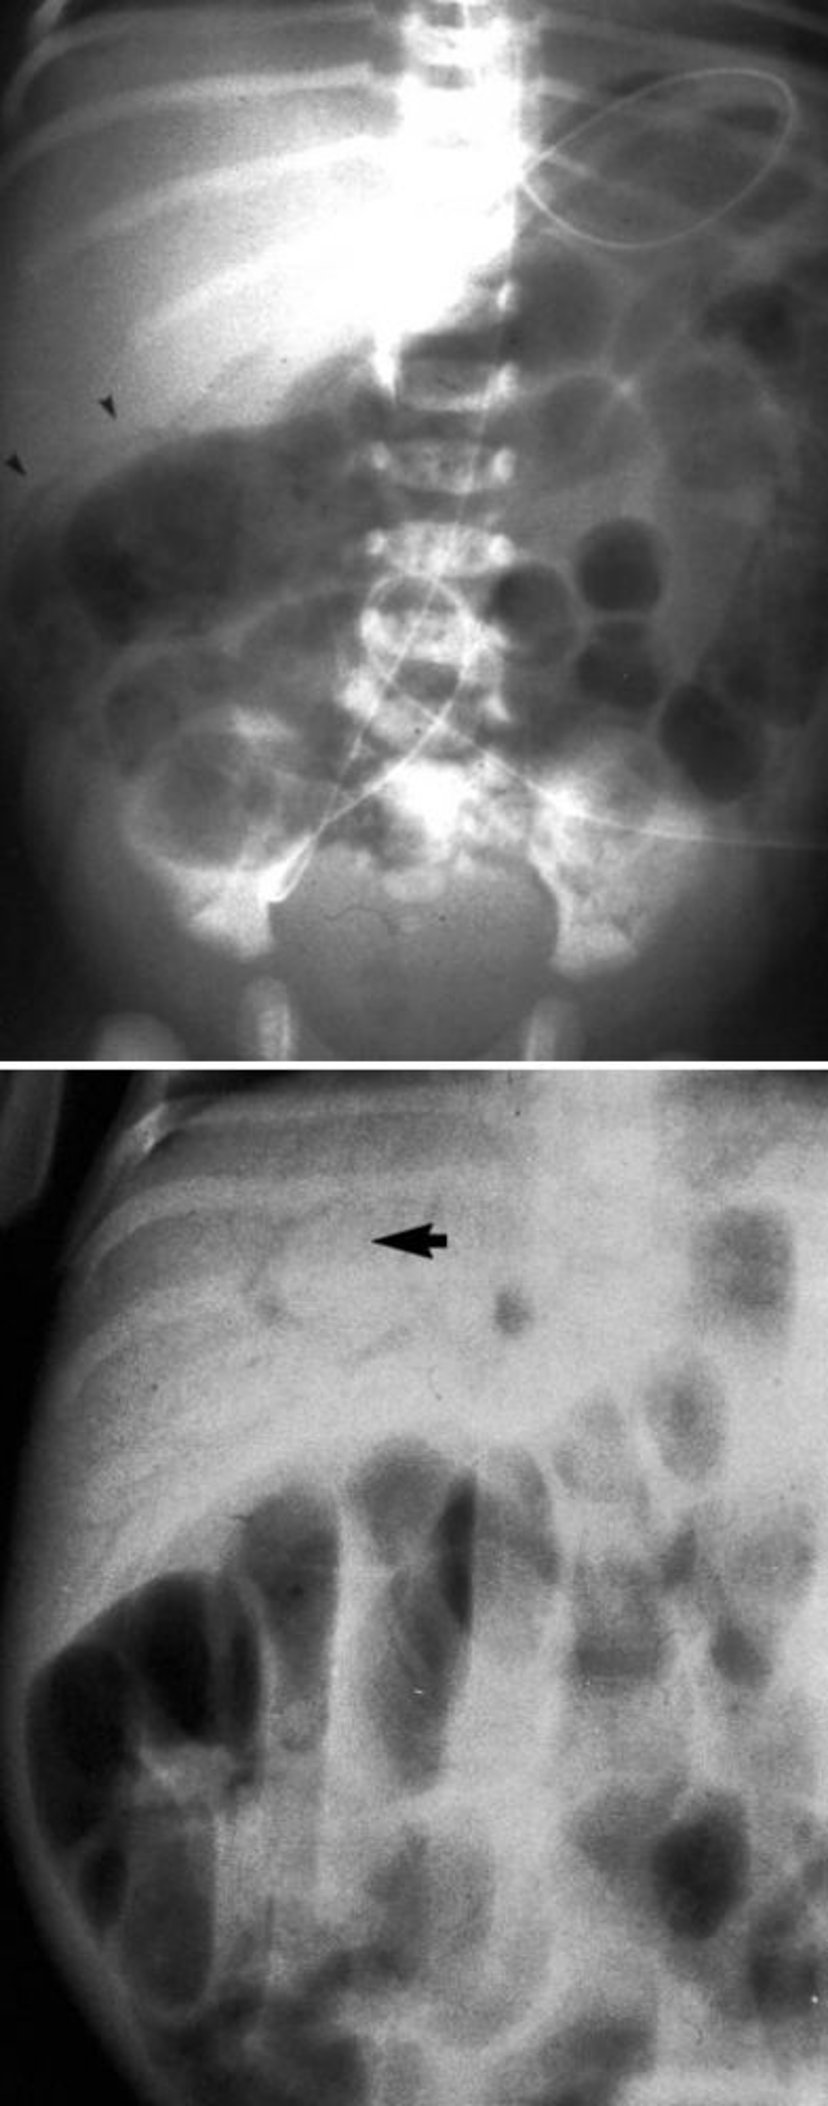

壊死性腸炎の放射線学的特徴

この画像では,腸壁気腫症(上,矢頭)および門脈内ガス像(下,矢印)が認められる。